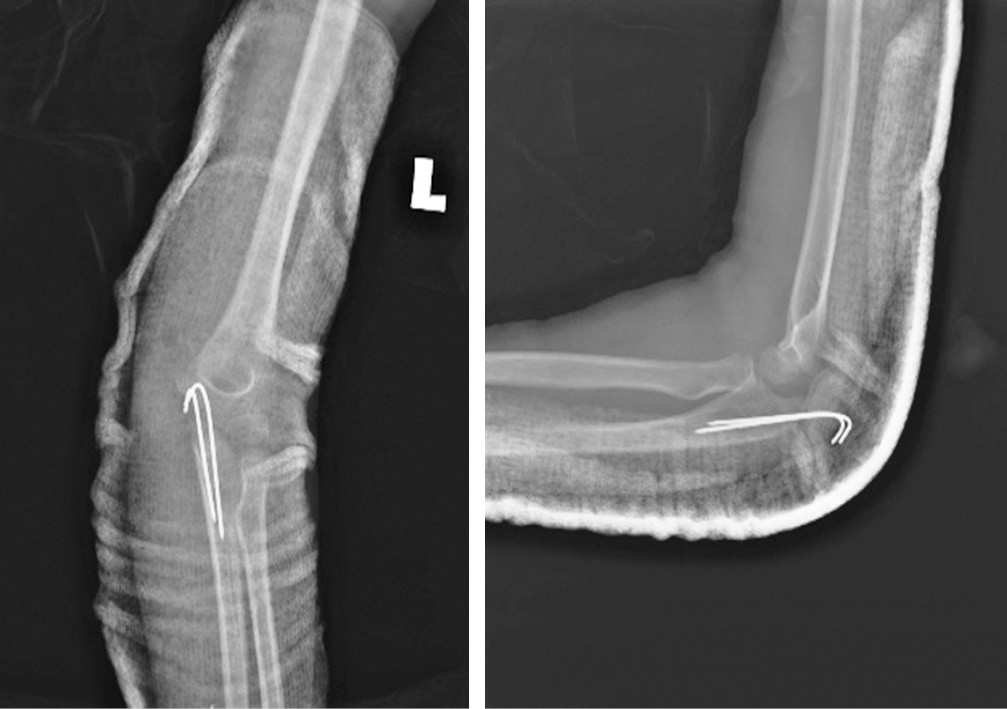

На обзорной рентгенограмме левого локтевого сустава выявлен передний вывих с переломом локтевого отростка (рис. 1). Примерно через два часа после травмы в отделении скорой помощи была предпринята попытка закрытого ручного устранения вывиха, которая оказалась неуспешной. Приблизительно через 6 ч после травмы под общей анестезией выполнено открытое устранение вывиха с чрескожной фиксацией спицей Киршнера. Для ревизии локтевого нерва и репозиции перелома выбран медиальный доступ. Интраоперационно обнаружено ущемление локтевого нерва дистальным фрагментом локтевой кости несколько дистальнее борозды медиального мыщелка. Нерв был натянут, его цвет казался слегка бледным, но целостность была не нарушена. Лучевой нерв был мобилизован проксимально и дистально до исчезновения натяжения. Перелом локтевого отростка произошел в области метафиза, при этом отломок кости был прикреплен в метаэпифизарной зоне, что соответствовало перелому II типа по Salter-Harris. Для репозиции выполнена осторожная контролируемая тракция за локоть. Перелом фиксирован двумя параллельными спицами Киршнера, репозиция головки лучевой кости была спонтанной. Полностью разорванная медиальная коллатеральная связка была восстановлена с помощью рассасывающейся нити 5/0. Интраоперационно оценена стабильность: локтевой сустав был стабилен в супинации, пронации, сгибании и разгибании. После репозиции и восстановления мягких тканей определялась хорошая пульсация на плечевой, лучевой и локтевой артериях. С помощью лонгеты локтевой сустав иммобилизован под углом 90° с предплечьем в положении супинации (рис. 2).

Рис. 2. Обзорная рентгенограмма левого локтевого сустава после операции. Вывих устранен, для стабилизации перелома локтевого отростка установлены спицы Киршнера